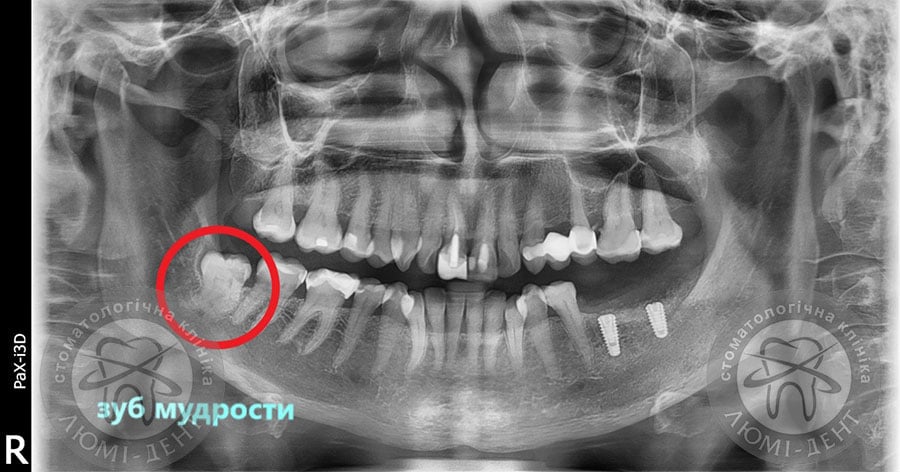

Рекомендуем в таких случаях обратиться в киевскую клинику Люми–Дент, не откладывая визит. У нас вы сможете провести диагностику и избежать возможных осложнений, которые способствуют развитию перикоронарита, абсцесса и прочих заболеваний. Безусловно, надо будет сделать рентгеновский снимок, который и покажет реальную ситуацию при прорезывании восьмерки. Чтобы упростить задачу хирургу, необходимо будет сделать также сканирование челюсти в формате 3-D, которое покажет точное размещение корней. У нас используют самые современные томографы модели Vatech PHT-6500. Они позволят сделать такой снимок дешевле, а доза облучения будет намного меньше, чем на обычном рентген-аппарате.

Как правило, если такие зубы правильно расположены, то они прорезаются в возрасте до 27 лет. Если они начали расти позднее, то могут не вырасти целиком или вызвать сложности. Однако заранее никто не может знать – как будет складываться ситуация. Есть люди, у которых эти зубы вообще отсутствуют – это можно увидеть на рентгеновском снимке.